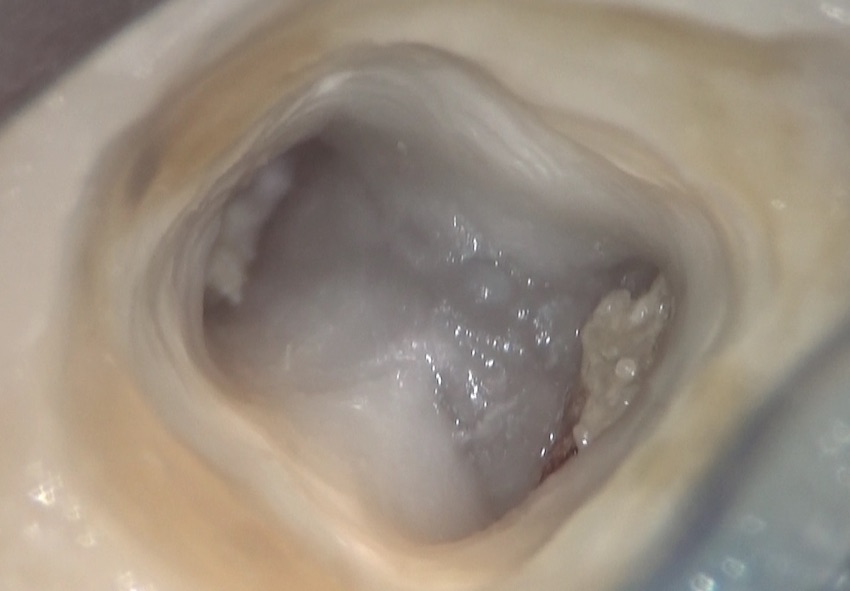

このあと、歯の内部にアプローチ、いわゆる根管治療を行うために、歯に穴を開けていきます。

この神経を洗い流し、この軟組織の入っている部分のその上の部分取り除いた部分です。左右に見えるのが、神経の管、つまり根管の入り口です。

この後、この内部の入り込んでいるかもしれない細菌を取り除き、また、これ以上細菌感染しないように、処置をしていくのが根管治療です。